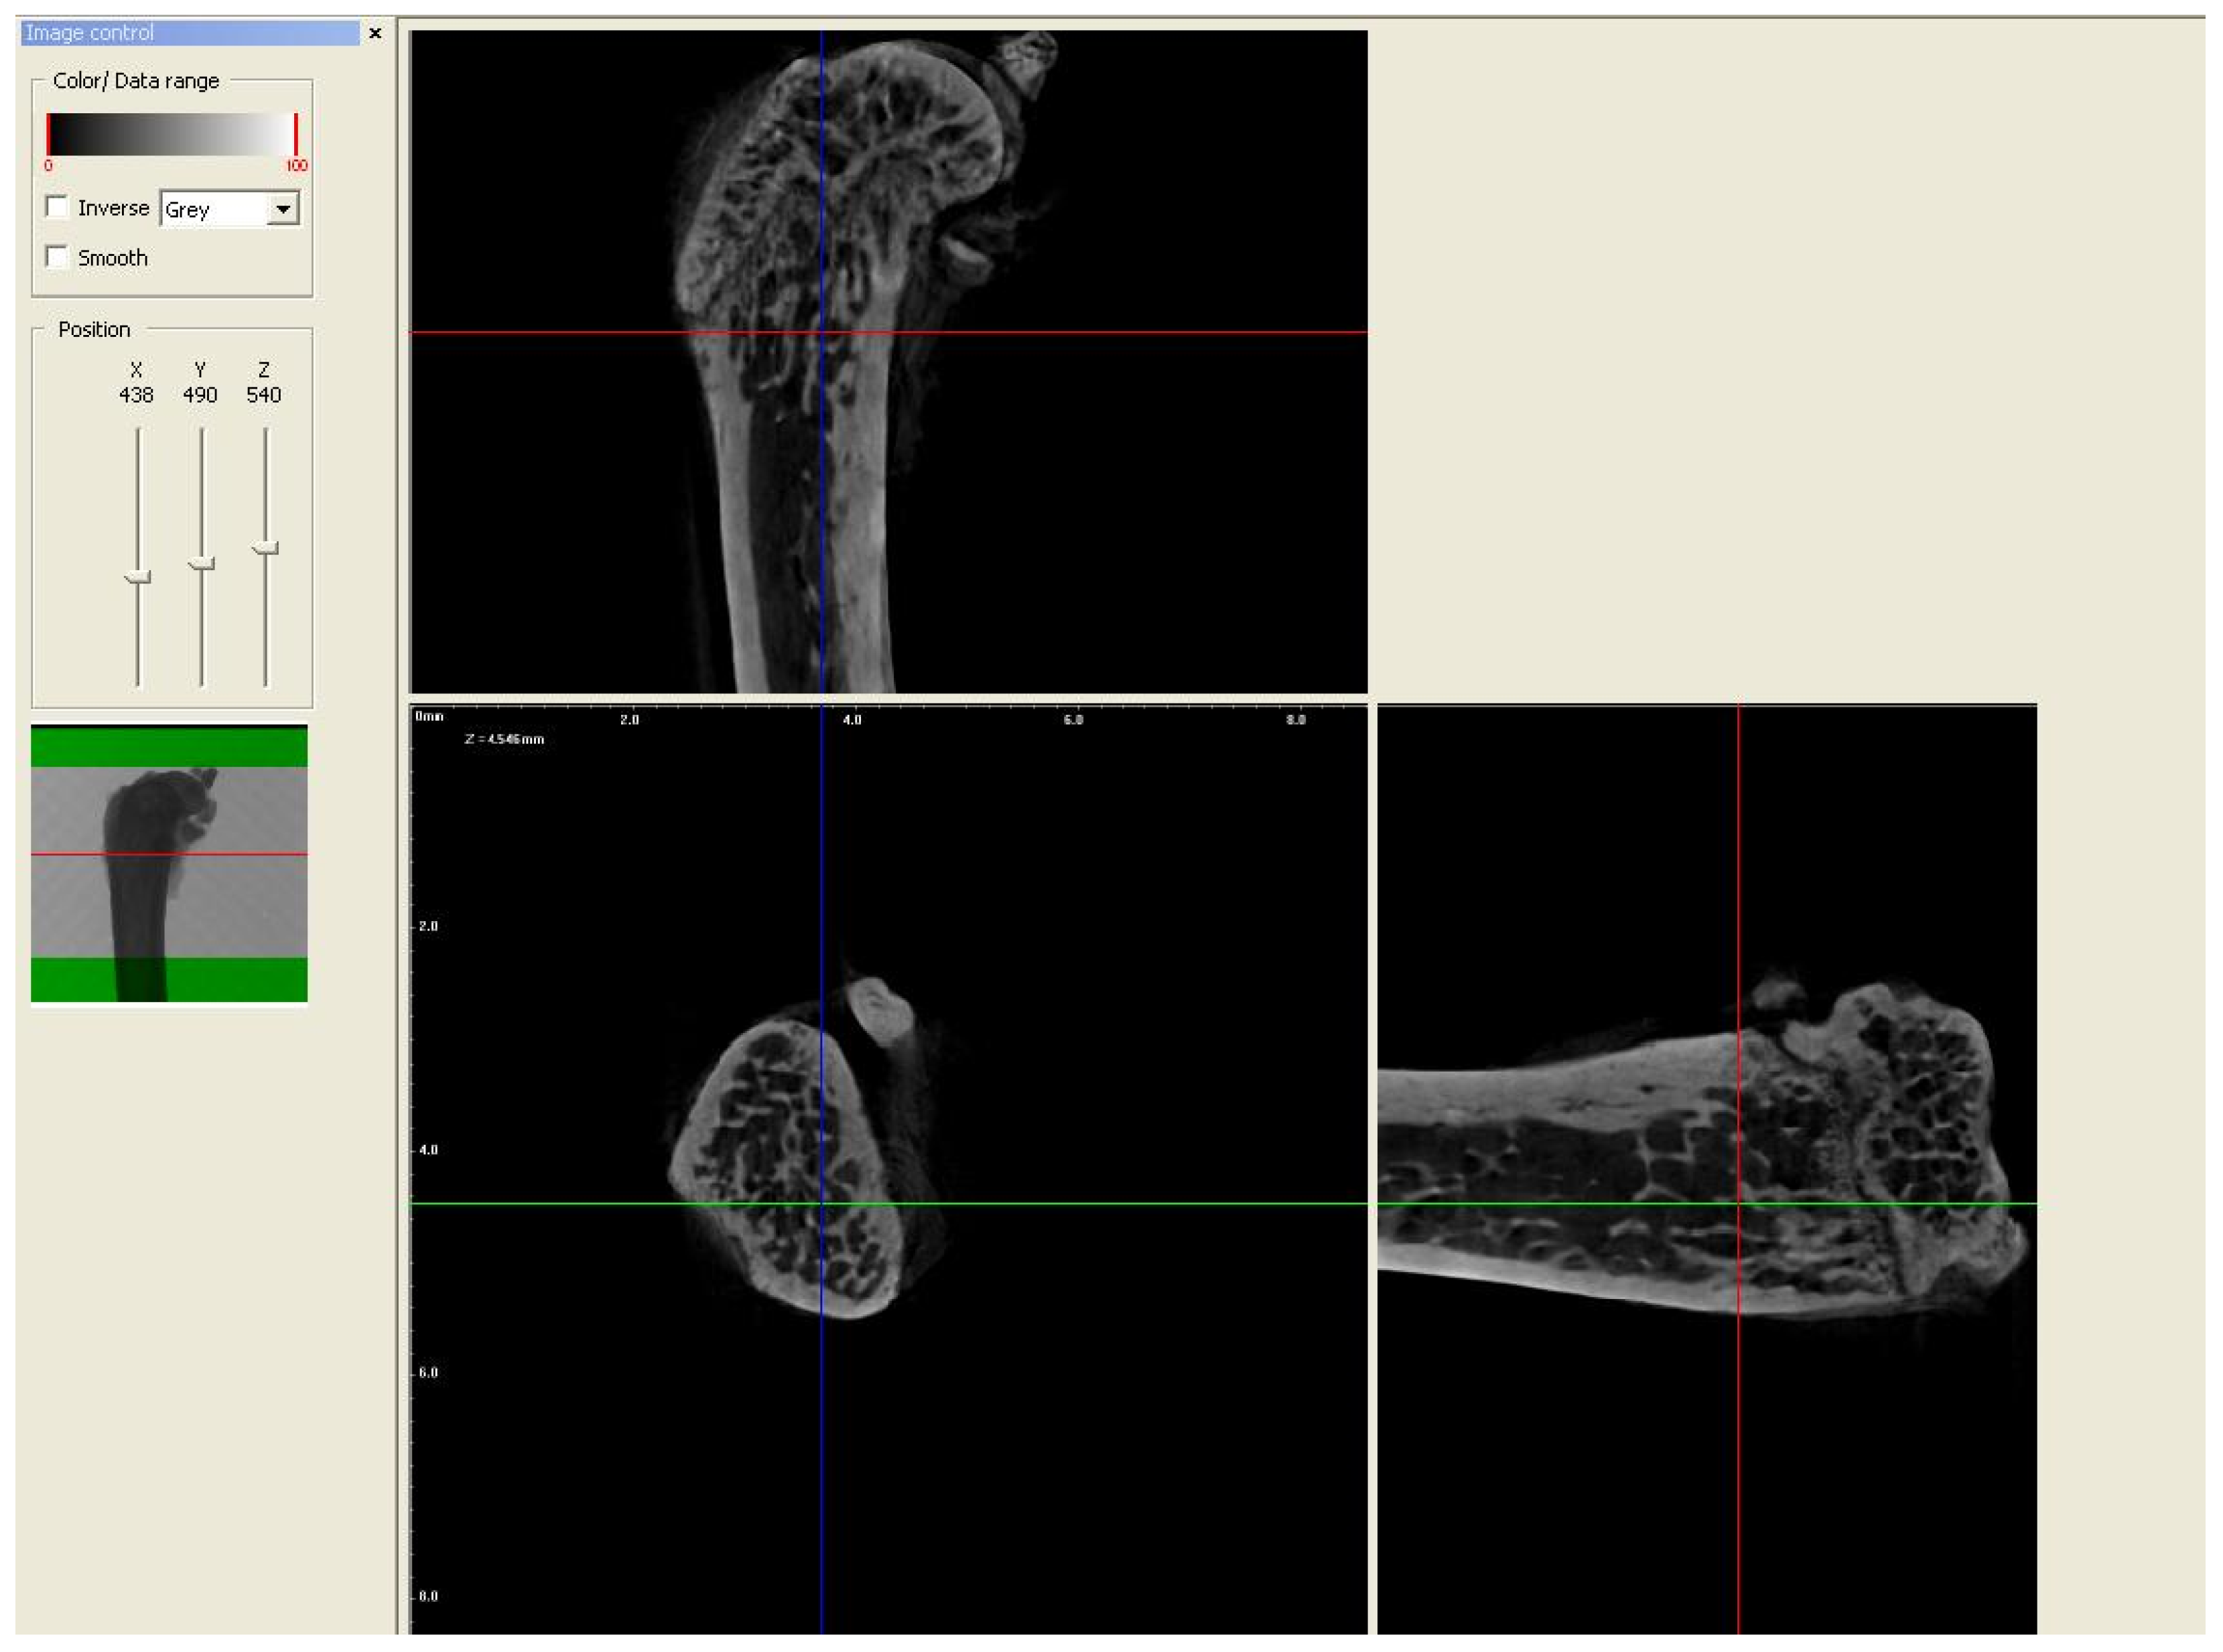

In order to evaluate the microarchitecture of bone tissue, the area of the distal metaphysis of the left femurs of all animals was subjected to microtomographic examination. After defrosting, the samples were placed on a centric stand in the center of the field of view of the microtomography chamber (Skyscan 1072, SkyScan, Antwerp, Belgium) and scanned (magnification 34×, Pixel 8.42, Rotation step 0.23, Exposure 1.9sec, and Gain 1). All of the samples were meticulously positioned so the mid-shaft of the bones was vertically straight and the orientation of the bones was consistent. Raw scans were reconstructed using the nRecon program (Skyscan, Belgium) and then thoroughly analyzed using the Ctan program (Skyscan, Belgium). An identical ROI (region of interest) was subjected to detailed morphometric evaluation. For the trabecular bone in all samples, a 100-slice cylinder was set in the central part of the distal epiphysis at a visual distance from the cortical bone, at the height of 85% of the bone length (Figure 1 and Figure 2). The analysis started at the most proximal end of the distal growth plate, which was visually identified in subsequent sections and taken as the reference point. In the ROI of each tested sample, the following microarchitectonic parameters were analyzed: percent of bone volume (BV/TV), trabecular thickness (Tb.Th), trabecular number (Tb.N), and trabecular separation (Tb.Sp). The surface of the cortical bone was assessed by subtracting the area whose outer border was the cortex’s inner circumference from the femur’s total surface at the level of the most proximal scan of the ROI from each group. Length measurements were measured from the left femur using a caliper. Representative micro-CT overview images are shown in Figure 3, Figure 4 and Figure 5.

Figure 3.

Representative overview photos for group control. The picture was taken during the micro-CT analysis (DataViewer SKYSCAN).